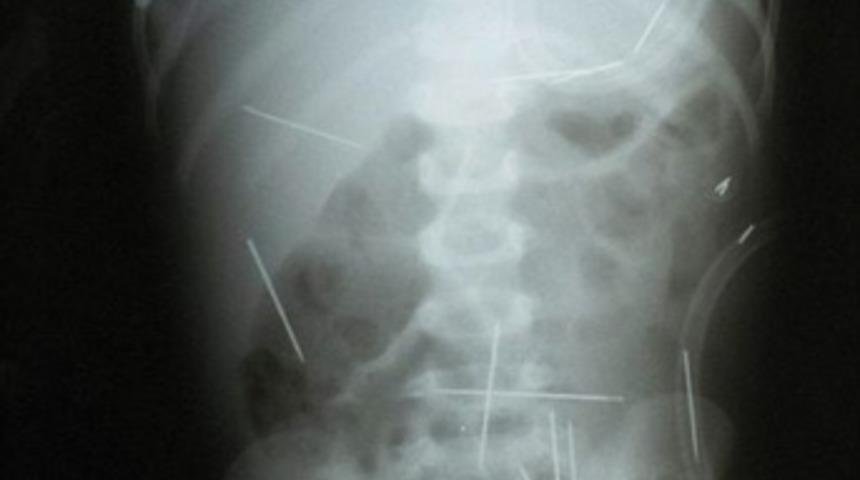

Röntgen filmindeki dehşet

Ağrıları olan 2 yaşındaki çocuk sürekli ağlıyordu. Doktor çekilen filmi görünce irkildi.

Brezilya'nın başkenti Brasilia'da, 2 yaşındaki bir erkek çocuğunun vücuduna 50 dikiş iğnesi saplandığı belirtildi.

Brezilyalı doktorlar, iğnelerin ameliyatla çıkarılacağını, ancak bazı iğnelerin, karaciğere yakın olması nedeniyle çıkarılmasının tehlikeli olacağını ve bu iğnelerin çocuğun vücudunda bırakılacağını kaydetti.

Polis, iğnelerin çocuğun vücuduna nasıl girdiğini araştırırken, Dr. Luiz Cesar Soltoski, iğnelerin tek tek saplandığının sanıldığını ifade etti.

Bazı iğnelerin çocuğun akciğerine de girdiği ve doktorların ameliyat için çocuğun nefes almasının düzelmesini bekledikleri belirtildi.